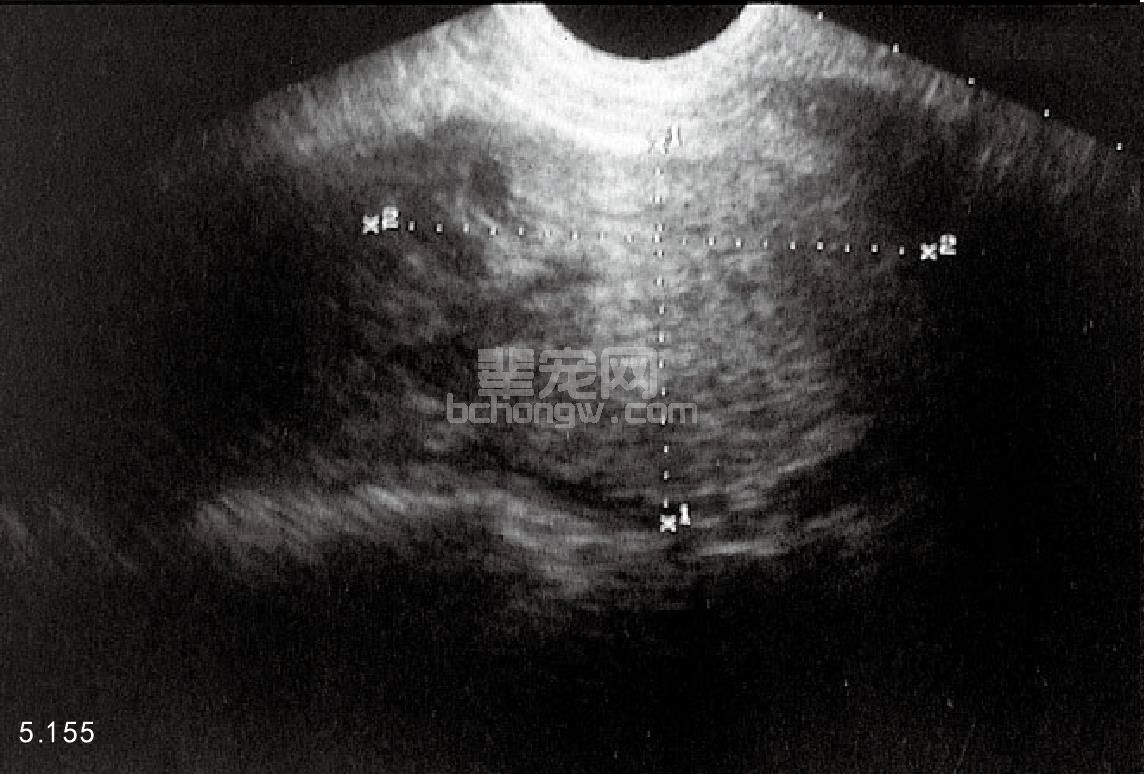

骨盆和腹腔的X线照相和超声波检查 超声波检查可以提供有关睾丸(图5.154)和附睾损伤与否及肿瘤、睾丸不下、睾丸扭转、腹股沟疝和前列腺的疾病(图5.155和图5.156)。超声波检查还可以用于前列腺穿刺针活组织检查和抽吸的监视。X线片有助于诊断腹腔后部的前列腺疾病。

图5.155 澳大利亚牧羊犬的横腹位超声图像,右半侧的前列腺增大聚集性囊状结构。